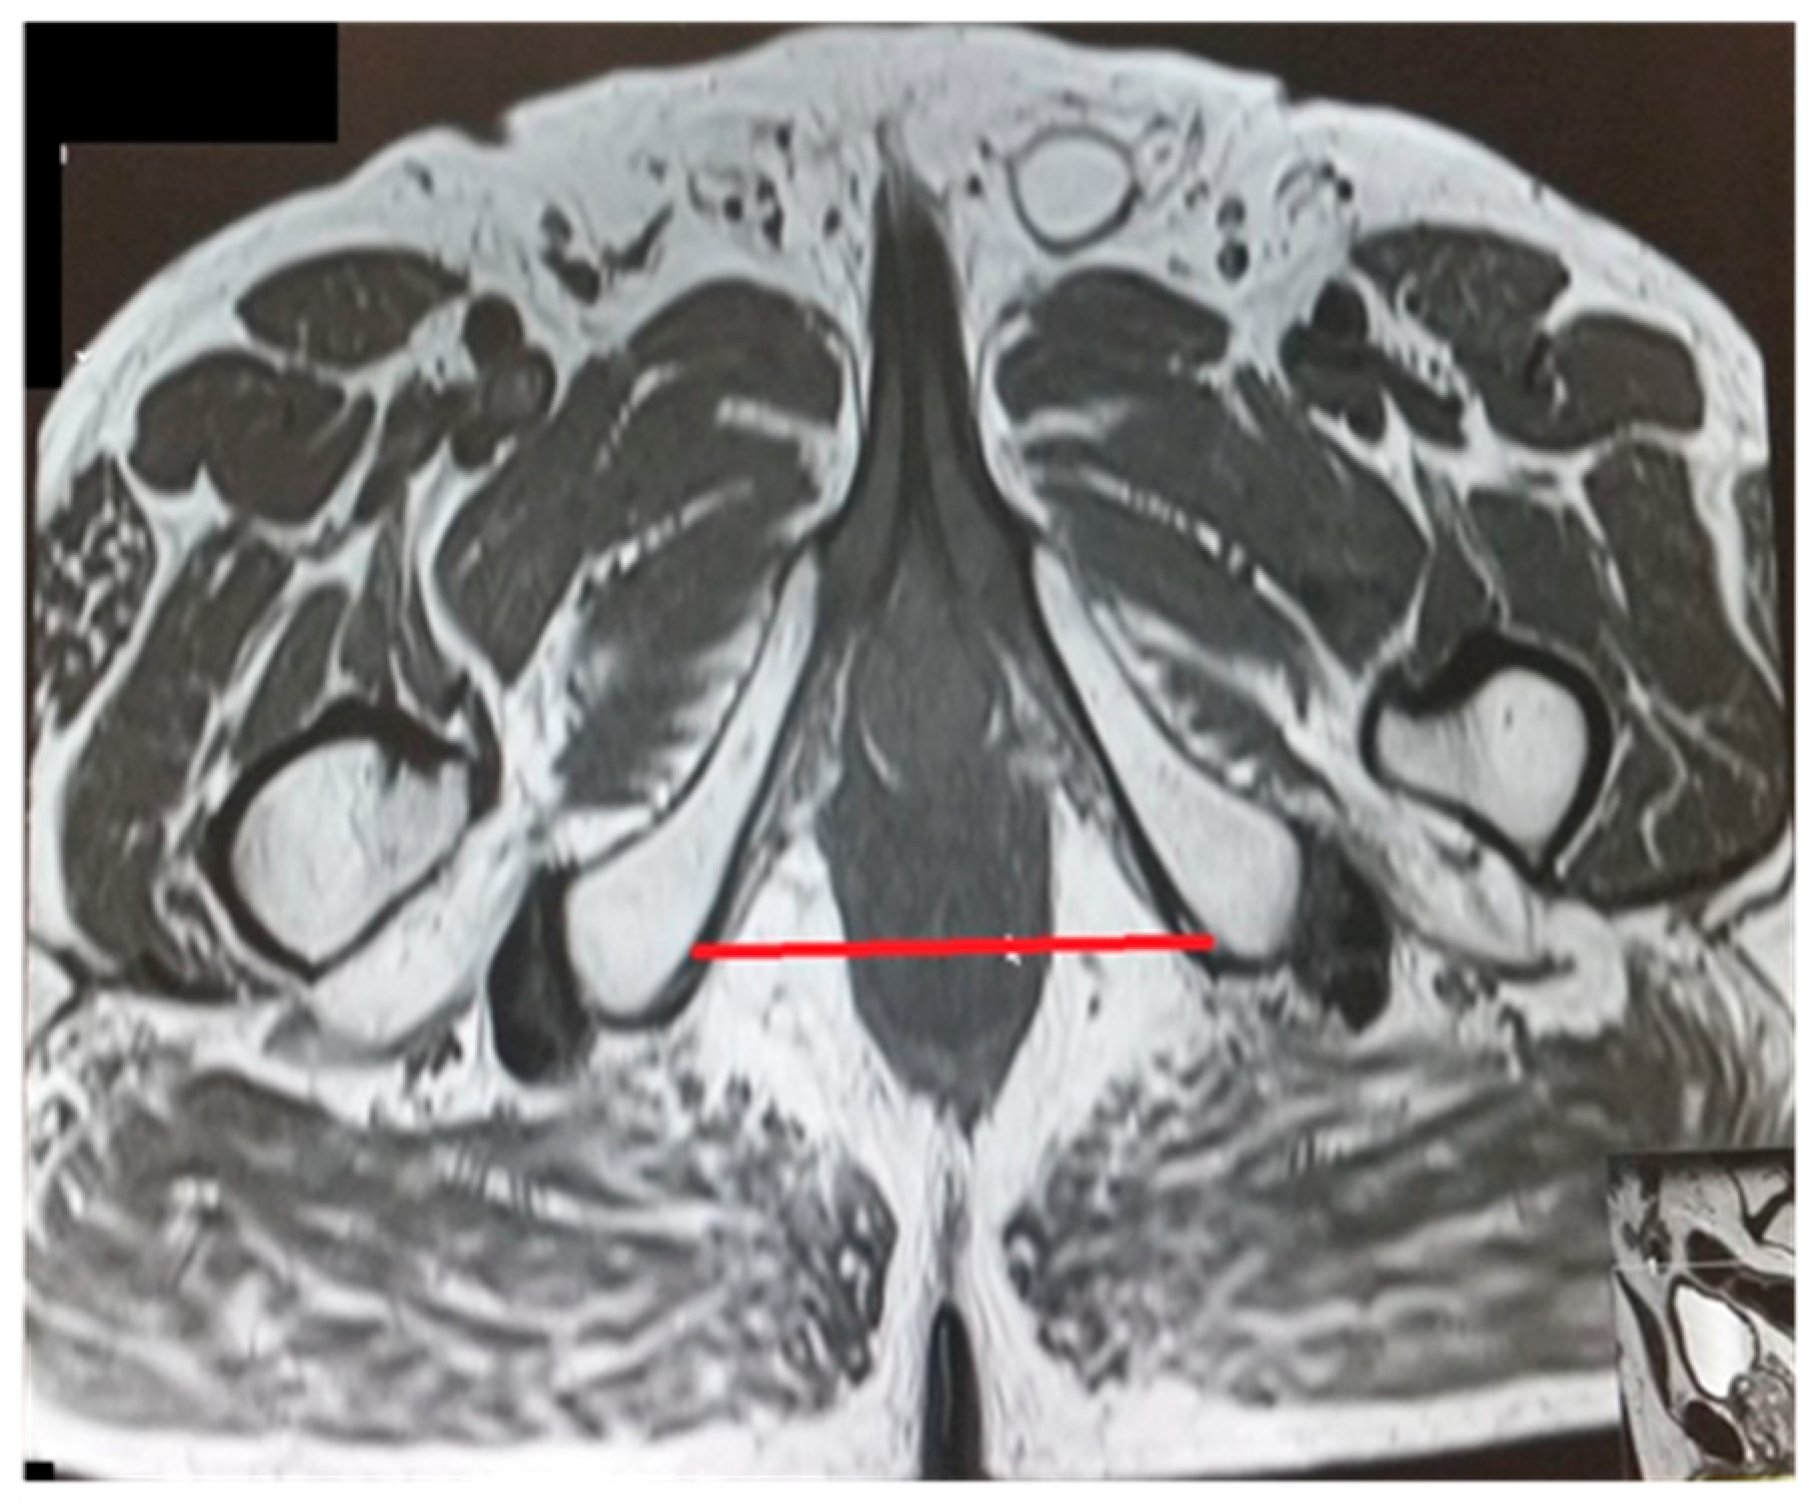

Figure 5.

Intertuberous distance.